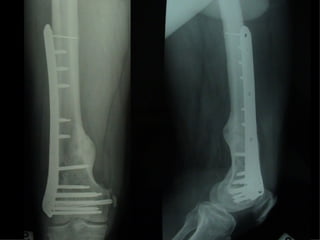

Dal Gennaio 2000 al Febbraio 2006 abbiamo trattato 167 fratture chiuse  con placca percutanea  in 164 pazienti :  27 lesioni diafisarie di gamba, 12 piloni tibiali ,  11 fratture prossimali di tibia, 36 fratture sovracondiloidee di femore, 17 fratture diafisarie di femore, 43 fratture metaepifisarie prossimali di omero, 21 diafisarie d’omero.  156 guarigioni 8 fallimenti

Dal Giugno 2002 al Dicembre 2004 abbiamo trattato 5 fratture esposte: 3 di tibia e 2 di ulna 5 guarigioni

I buoni risultati ottenuti dipendono da 5 punti fondamentali:   una accurata riduzione percutanea della frattura  precise vie di accesso  l’utilizzo della placca che consenta il più lungo braccio di leva possibile il pretensionamento della placca  una sintesi con un ridotto numero di viti

Precise vie di accesso

Placche lunghe e pretensionate

Placche lunghe e pretensionate Sintesi con un ridotto numero di viti